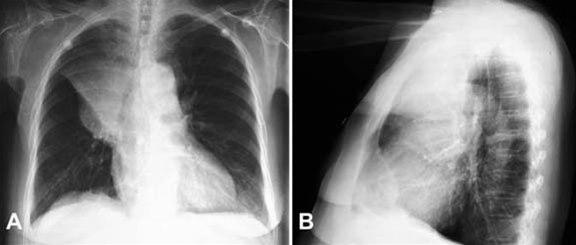

Lungekreft, front og side

Frontal- og sidebilde av et bronkogent karsinom som har forårsaket sammenfall av øvre høyre lungelapp.